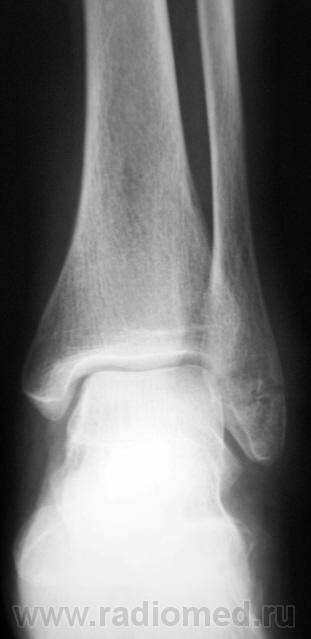

перелом наружной лодыжки без смещения отломков.

Похоже на перелом лодыжки, есть все признаки, но где то подвох, ведь Валентин Львович банальный перелом лодыжки, которые десятки в день проходят, на сайт бы не выставил

Ну, что Вы? Ну какой подвох?